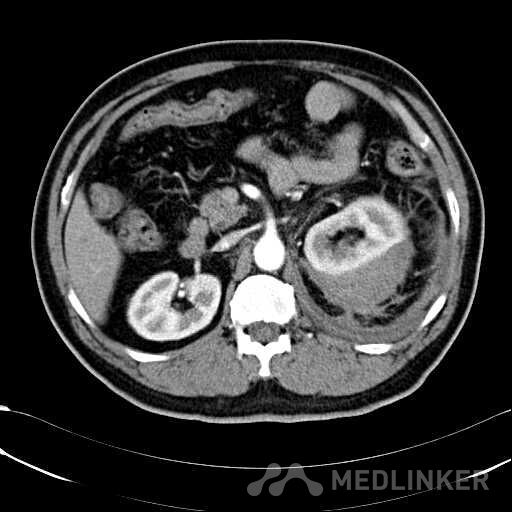

患者是54岁男性 主 诉: 突发左腰部疼痛3小时。 现病史: 缘于入院前3小时患者无明显诱因出现左腰部剧烈疼痛,无向他处放射,与活动及体位无明显关系,伴有腹胀、恶心、呕吐,无头痛、头晕,无人事不省、口吐白沫,无胸闷、胸痛、咯血,无发热、畏冷、寒战,大小便未解,肛门无停止排气,遂就诊我院,查“泌尿系彩超:左肾实质及不均质回声区,范围约9.4*4.1cm,界不清,内未见明显血流信号”,为进一步治疗,门诊拟“左肾占位”收住入院,发病以来,患者精神欠佳,未进食,大小便如前述,体重无明显改变。 患有“高血压病”7年,规则服药治疗(具体不详),监测血压情况不详。 T: 36.5 ℃ P: 65 次/分 R: 20 次/分 BP: 154/94 mmHg 双肾区皮肤无红肿、破溃及隆起,双肾肋下均不能被触及,左侧肾区叩击痛明显,右侧肾区无叩击痛,双侧肾区未闻及血管杂音。膀胱区无隆起,无压痛,耻骨上膀胱区叩诊空虚。外生殖器发育正常。 2016-04-12 泌尿系彩超:左肾实质及不均质回声区,范围约9.4*4.1cm,界不清,内未见明显血流信号。 04-12血常规:血红蛋白 151 g/L,白细胞 16.80 10^9/L,中性粒细胞百分比 84.90 %。急诊生化:白蛋白 39.8 g/L,葡萄糖 9.46 mmol/L。